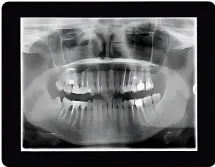

Digital X-rays are a cornerstone of modern orthodontic care, allowing us to see detailed images of your teeth, jaw, and surrounding structures with incredible clarity. Unlike traditional X-rays, which involve higher levels of radiation and slower processing times, digital X-rays are safer, faster, and more precise.

The immediate availability of digital images means Dr. Matt can analyze and diagnose issues on the spot, creating a tailored treatment plan during your appointment. This technology is particularly valuable for identifying hidden orthodontic concerns, such as impacted teeth, jaw alignment issues, or bone health problems that may not be visible to the naked eye. By catching these issues early, we can prevent complications and ensure your orthodontic treatment is as smooth and effective as possible.